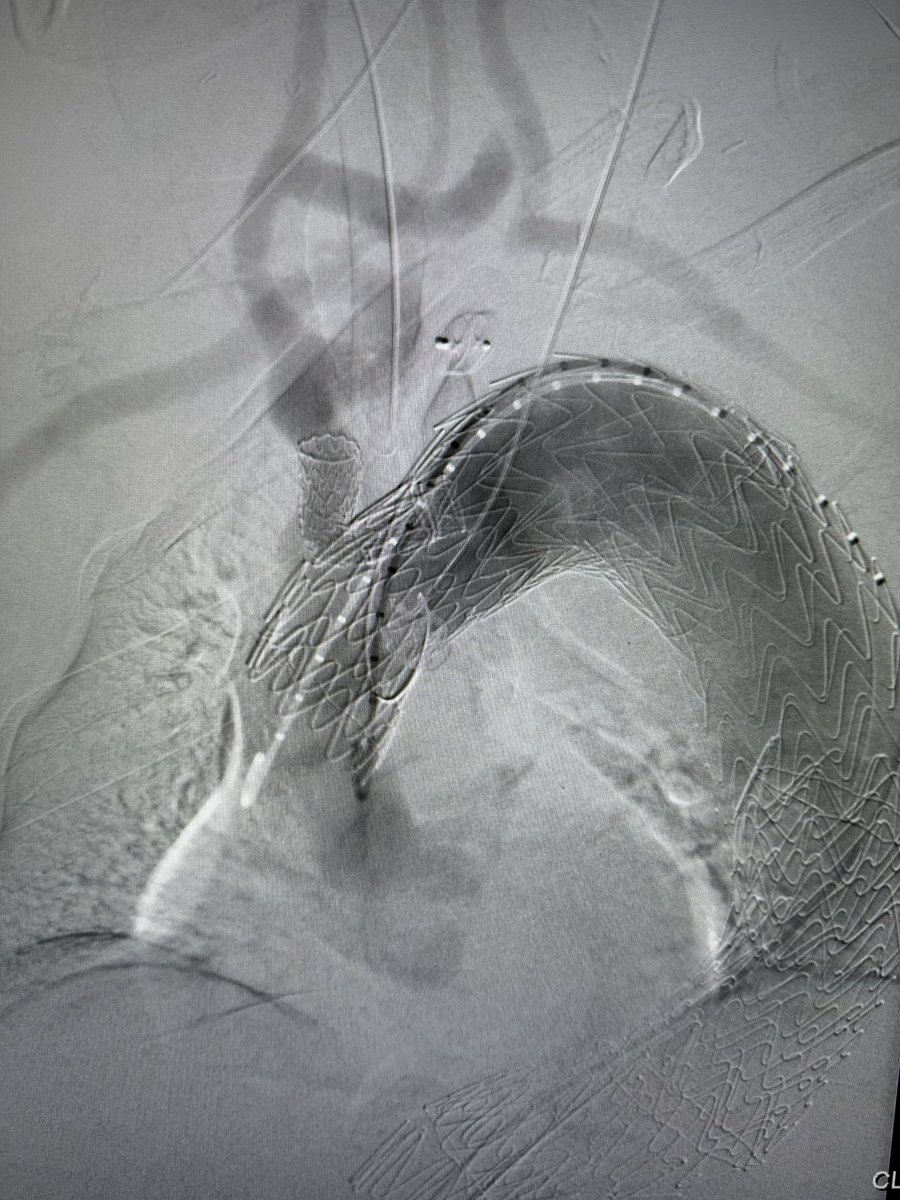

Dr Michael Wilderman

Chief of Endovascular Surgery and Co-Director of Aortic Center at Hackensack University Medical Center